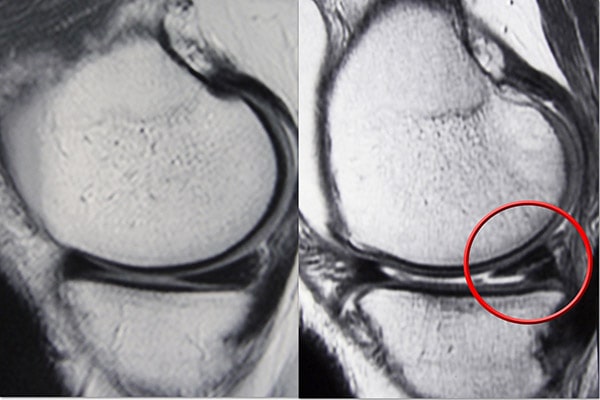

磁共振成像 (MRI) 掃描。  MRI 掃描可評估膝關(guān)節的軟組織,包括半月板、軟骨、肌腱和韌帶。

MRI 掃描顯示(左)正常的半月板和(右)撕裂的半月板。撕裂可以看作是穿過(guò)半月板黑色主體的白線(xiàn)